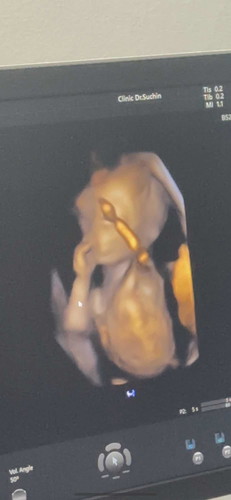

อัลตร้าซาวด์4มิติ ตอน15วีค

ครั้งแรกที่ตั้งใจไปซาวด์อยากรู้เพศ น้องก็โชว์แม่ๆเลยคะ เป็นผู้ชาย ทีมมิถุนายน 68 * รู้สึกว่าคนคลอดเดือนนี้ได้ผู้ชายกันเยอะมากกก แม่ๆบ้านไหนได้ลูกสาวบ้างคะ ฮื๊ออ #ขอความคิดเห็นของคุณแม่หน่อยค่ะ อิจเบาๆ อิอิ🥹🥰